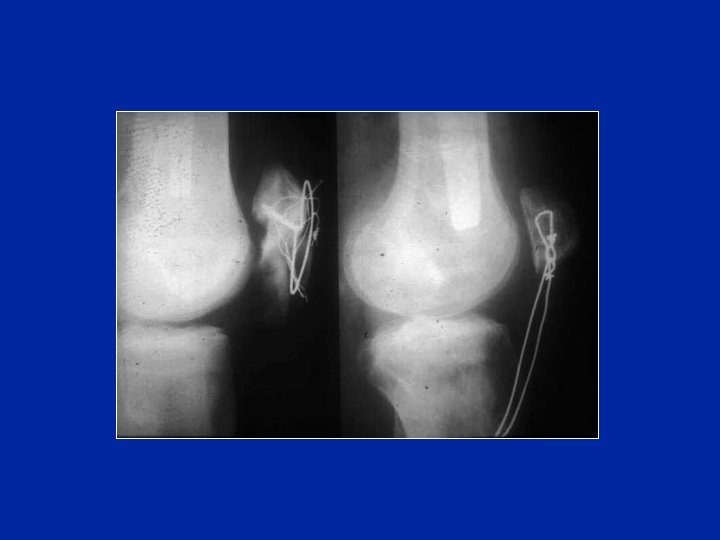

Cerchiaggio di cattiva qualità

Ripresa per un haubannage di cattiva qualità!

Cedimento hauban che evolve in una pseudoartrosi

Trattamento per rivitalizzare la pseudoartrosi e compressione con un nuovo hauban

Risultato 12 anni dopo Buona flessione, buona funzione, rimaneggiamento della rotula e dell’interlinea